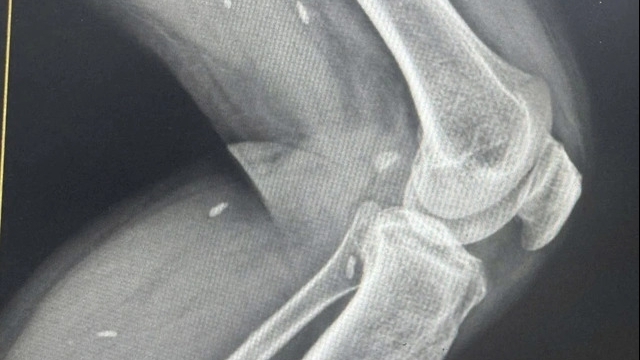

Các y, bác sỹ Bệnh viện Đa khoa Hữu nghị 103 Yên Bái thực hiện tiểu phẫu gắp mảnh kính găm vào chân cho anh Nguyễn Mạnh Thắng, chiến sĩ Lữ đoàn 297, Quân khu 2 bị thương trong khi đi hỗ trợ người dân dọn dẹp vệ sinh môi trường sau lũ. (Ảnh: Báo Yên Bái) |